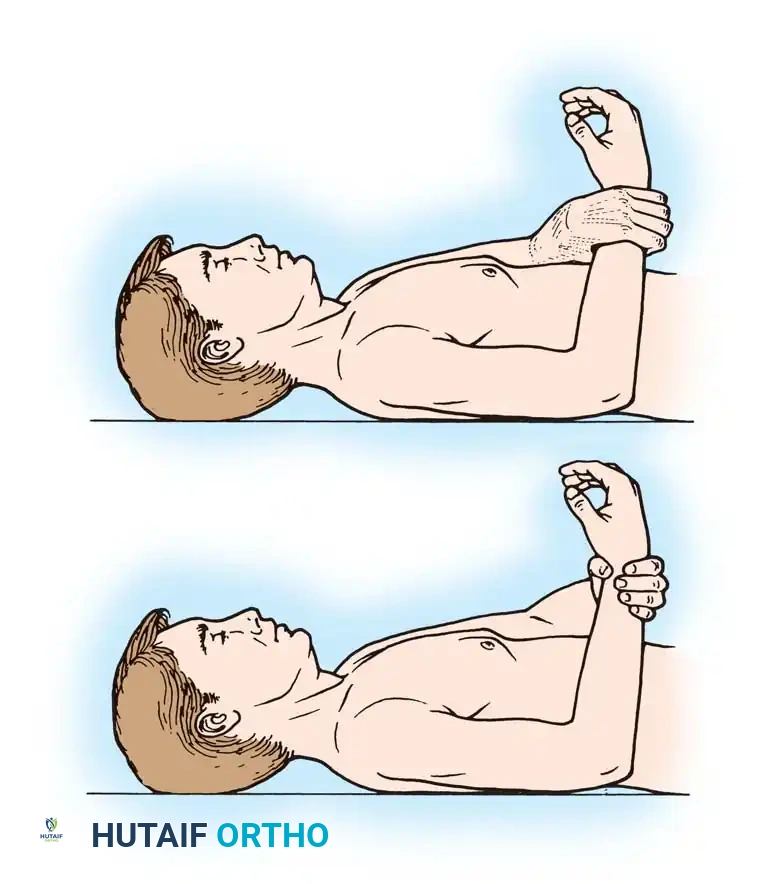

Shoulder Arthroplasty Rehabilitation

- Phase I (0-4 weeks): Sling immobilization. Passive range of motion (PROM) only. Strict avoidance of active internal rotation and passive external rotation beyond 30 degrees to protect the subscapularis repair.

- Phase II (4-8 weeks): Discontinue sling. Begin active-assisted range of motion (AAROM). Initiate isometric deltoid exercises.

- Phase III (8-12 weeks): Progress to active range of motion (AROM) and light resistance training.

- Phase IV (3+ months): Advanced strengthening. Return to light recreational activities (e.g., golf, swimming) is typically permitted at 4 to 6 months. Weight-lifting restrictions (usually < 25 lbs) are permanent to prevent glenoid loosening.